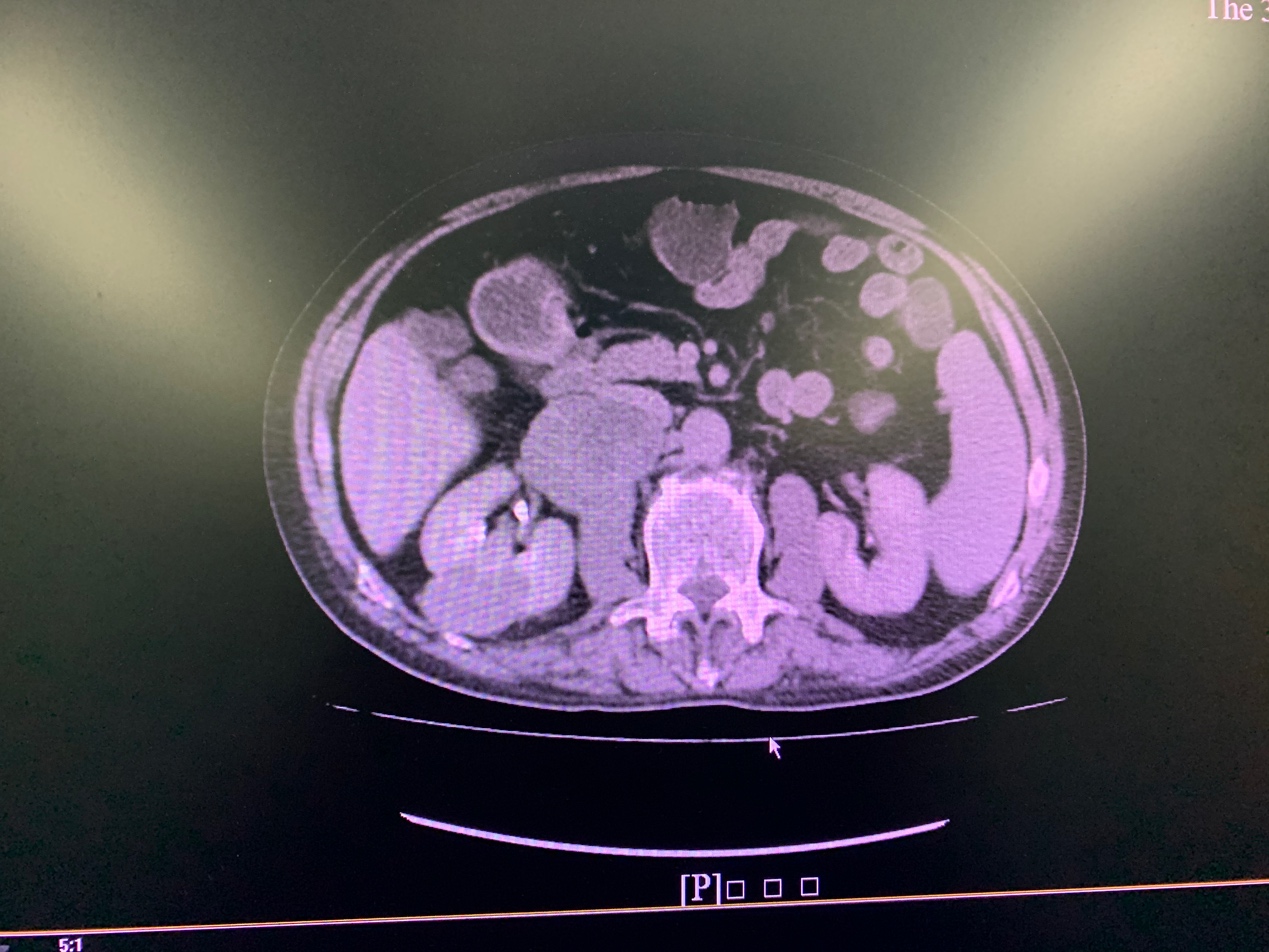

患者男性,70岁,因左髌骨骨折住院检查发现右肾癌伴腹膜后转移,入院后CT及磁共振检查提示右肾癌伴腹膜后淋巴结转移,转移灶体积巨大,右肾动静脉受压移位,下腔静脉,十二指肠与肿物粘连,手术切除难度极大,风险极高。

全息影像技术通过处理加工患者的CT及MRI影像数据资料,呈现出高保真的全息立体影像。通过全息影像,医生可以看清人体内部复杂器官的相对位置,清晰显示肿瘤与周围血管,器官的相对关系,全方位透视肿瘤,为术者在手术全程提供参照,大大缩短了手术时间,提高了手术安全性。

南医三院泌尿外科是目前广东省开展单孔腹腔镜技术最为成熟的单位,现又紧跟时代潮流,率先运用了全息影像与单孔腹腔镜影像融合技术,为该高龄复杂肾癌患者完成了单孔腹腔镜下右肾癌根治性切除术。该技术在肾癌根治性切除过程中,通过融合影像快速定位肿瘤的位置、边界以及血管分布情况,帮助手术医生更快更安全地切除了右肾癌及转移的淋巴结。